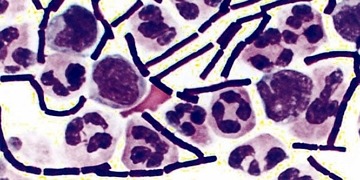

DevamıEnfeksiyon mikrop ve virüslerin vücuda bulaşması ile gelişir. Pek çok türü vardır ve doğru şekilde tedavi edilmeyen bazı enfeksiyonlar ölümcül olabilir.